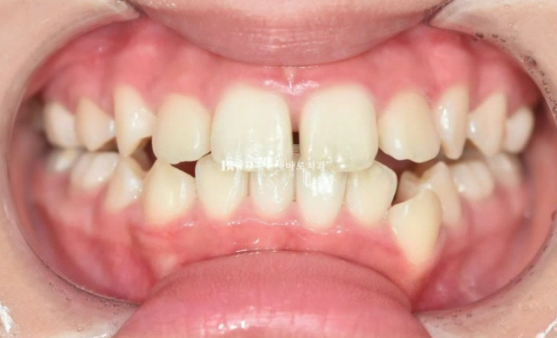

22년 7월 본원에 교정치료를 위해 내원한 만 10세 어린이 입니다.

이미 다른 소아치과에서 교정 중 내원했고 모델활동하는 친구여서 앞니가 가지런해야 했습니다.

앞니는 가지런해졌지만 비대칭을 고치고 싶어하셨습니다.

엑스레이 분석 상 턱의 비대칭은 아니였고 단지 치아 중심선이 틀어진 것이므로 교정으로 해결이 가능했습니다.

실제로 얼굴 전체로 보면 인중에 비하여 위 앞니 중심선이 한쪽으로 쏠려있었습니다.

오른쪽 교합은 나쁘지 않습니다.

23.08

왼쪽은 3급 교합관계 때문에 왼쪽 어금니는 잘 안 물리고 이것이 앞니에 영향을 주어 위 앞니 중심이 인중과 얼굴에 비하여 틀어져 있습니다.